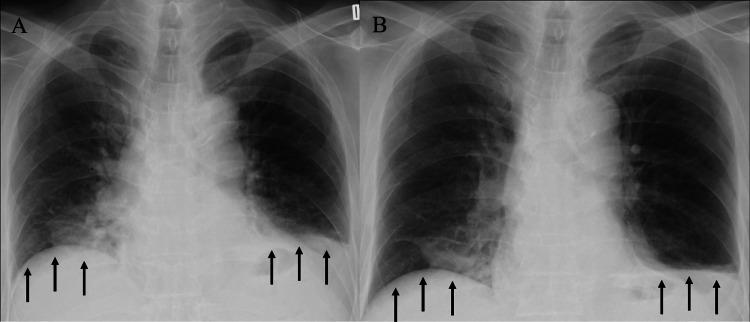

Bilateral diaphragmatic nerve paralysis due to cervical spondylosis is an extremely rare condition with only one previously reported case. We present a 64-year-old Japanese male with a history of left diaphragmatic nerve paralysis who developed sudden nocturnal dyspnea. Physical examination revealed orthopnea and type 2 respiratory failure. Imaging studies showed bilateral diaphragmatic elevations and cervical spine stenosis at C3/C4 and C4/C5 levels. Pulmonary function tests demonstrated a significant reduction in vital capacity, particularly in the supine position. After excluding other potential causes, the diagnosis of bilateral diaphragmatic nerve paralysis secondary to cervical spondylosis was established. The patient was successfully treated with noninvasive positive pressure ventilation (NPPV) and showed gradual improvement in symptoms and diaphragmatic function over three years of follow-up. This case highlights the importance of considering cervical spondylosis as a potential etiology for bilateral diaphragmatic nerve paralysis and demonstrates the effectiveness of NPPV in managing this rare condition. Regular monitoring and long-term follow-up are crucial for optimal management of these patients.